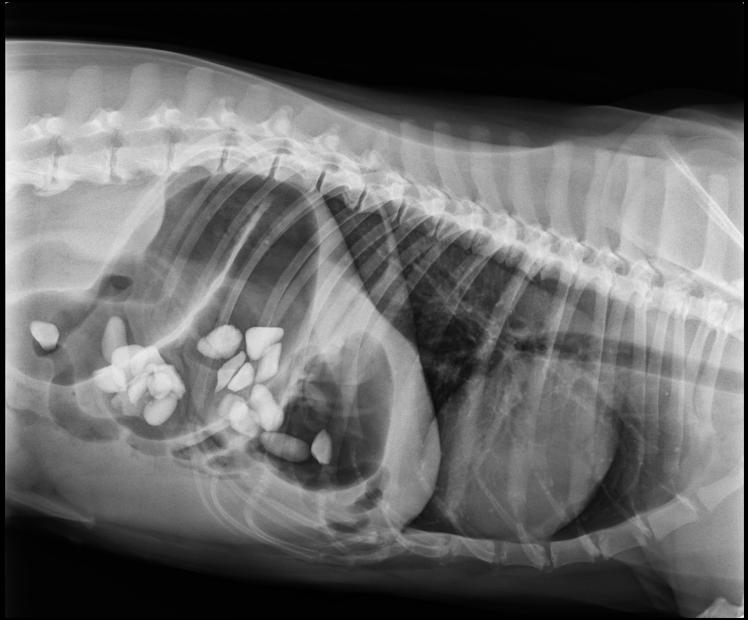

A volte il corpo estraneo risulta evidenziabile alla visita clinica, spesso pero’ bisogna ricorrere a specifici esami come la radiografia. Quelle macchioline bianche che vedete sono infatti un tot di sassi che la nostra amica Layla si è voluta mangiare.

I signori proprietari sono avvisati! Gli aspirapolvere non sono solo quelli che vanno ad energia elettrica.